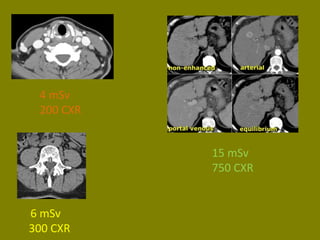

4 mSv

200 CXR

6 mSv

300 CXR

15 mSv 750CXR 4 mSv 200 CXR 6 mSv 300 CXR